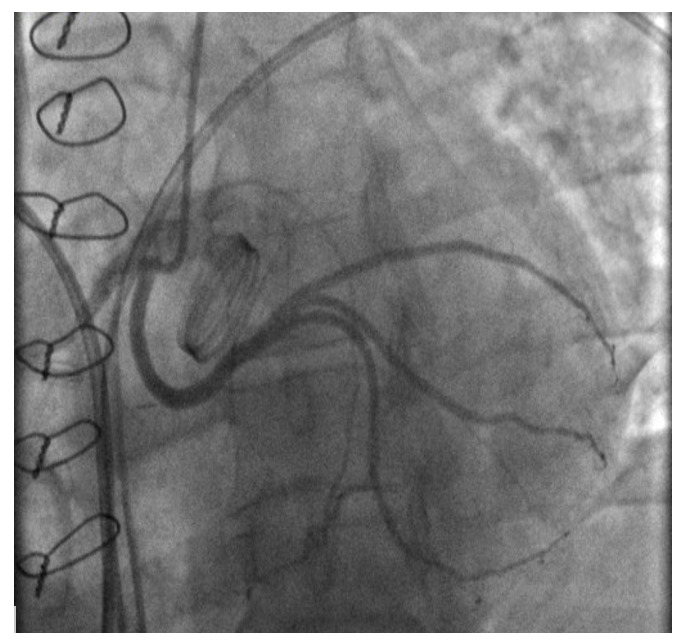

A 45-year-old male (height 168 cm, weight 95 kg, body mass index 33.7, body surface area 2.04 m2) with chest pain was admitted via ambulance to the clinic at his place of residence. During the examination, the patient had a paroxysm of ventricular tachycardia, stopped by medication. According to the ECG data, signs of hypertrophy of the left ventricle (LV) with subepicardial damage to its anterior parts were revealed. After performing thrombolysis (Actilyse (Boehringer ingelheim pharma, GmbH & Co.KG, Germany) 100 mg for 90 minutes), the patient was transferred to our Center for the further treatment. At the time of admission, there was a significant elevation of troponin I levels to 101 ng / ml with progressive decreasing in the follow. Coronary angiography showed no hemodynamically significant stenosis of the coronary arteries, but an anomalous origin of the left circumflex artery from the RCA was noted (Fig.1B). Myocardial injury was regarded as a type 2 myocardial infarction due to ventricular tachycardia paroxysm. Echocardiography revealed severe aortic stenosis with an aortic valve area 0.88 cm², a peak acceleration of blood flow of 4.2 m/s, an average pressure gradient of 42 mmHg, and the diameter of the AV fibrous ring 21 mm. LV hypertrophy was noted: posterior and interventricular septum of 18 and 15, respectively. Also, no regional areas of contractility disorders were noted. Taking into account the acute stage of type 2 myocardial infarction and severe aortic stenosis surgical treatment were postponed for 4-6 weeks. During rehospitalization for the surgical treatment CTA was performed to clarify the anatomical features of the aortic root and coronary arteries (Fig.1A).

After median sternotomy, cardiopulmonary bypass was established via proximal aortic arch and right atrial cannulation, and systemic cooling was initiated targeting a nasopharyngeal temperature of 32 °C. Following aortic cross-clamping and cardiac arrest achieved by retrograde blood cardioplegic perfusion to the coronary sinus. After the mobilization of the aortic root and ascending aorta the anomalous LCx was identified at its origin of the right coronary button coursing down toward the noncoronary sinus of Valsalva (Fig.2A). LCx was mobilized from the side of its origin till the middle third of the left coronary sinus (the zone where LCx is located 15-20 mm below the left coronary artery). After aortotomy, coarse grained calcified unicuspid aortic valve was revealed. Upon direct measurement of the aortic valve annulus with standard calibers, the diameter of the aortic valve fibrous ring was 21 mm. A patient-prothesis mismatch and possible damage to the anomalous LCx were the main reasons to make a decision toward performing AVR with an aortic root enlargement by Nicks (Fig.2B) The aortotomy was extended through the non-coronary sinus and the fibrous ring of the AV to the base of the anterior leaflet of the mitral valve. A wedge-shaped bovine pericardium patch 30x50 mm (KemPeriplas-Neo Xenopericardial, Kemerovo, Russia) used to repair of aortic root and aortic valve fibrous ring. Further, a bicuspid mechanical prosthesis Medtronic Open Pivot AP360 23 mm (Medtronic plc, Minneapolis, Minnesota, USA) was implanted into the aortic valve position with 19 “U”-shaped sutures on Teflon pads (PremiCron 2/0): 9 sutures were located on the aortic side, 6 on the left ventricular side, 4 on the outside of the xenopericardial patch). Postoperative transesophageal echocardiography confirmed excellent prosthesis valve function, and no regional disorders of the LV were revealed.